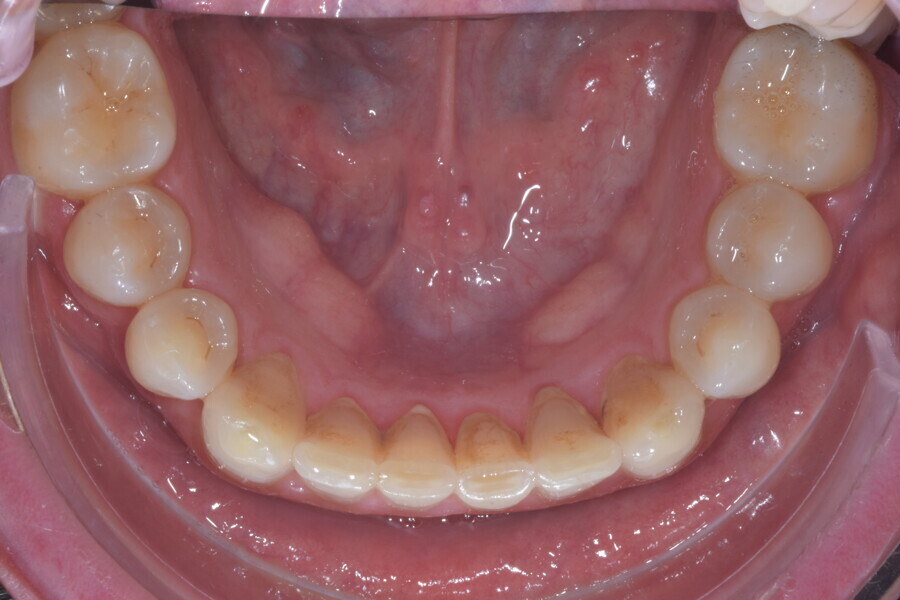

Fig. 13

Fig. 14

Fig. 15

Fig. 16

Fig. 17

Fig. 18

A 37-year-old male patient presented with the chief need for re establishing anterior alignment in both arches. Facial analysis showed a short face with a flat profile but proper chin projection (Figs. 9–12), and clinical examination revealed a skeletal Class I (ANB = 0.89°) and dental Class I malocclusion with severe deep bite (almost 100%), a deep curve of Spee, normal maxillary central incisor torque (Ui–FH = 110°), mild maxillary crowding and moderate mandibular crowding (Figs. 13–18). The deep bite components were represented in this patient by the severe skeletal condition of hypo divergent pattern (FMA = 14.24°) with normal maxillary and mandibular incisor inclination and decreased gonial angle (110.46°). Analysis of the cephalometric radiograph indicated a reduced lower anterior facial height, combined with a hypo-divergent pattern (Fig. 19). The only treatment option suggested was orthodontic treatment with aligners for deep bite correction with all the features described (bite ramps, pressure area, 3D curve of Spee levelling, Class II elastics and heavy occlusal contacts).